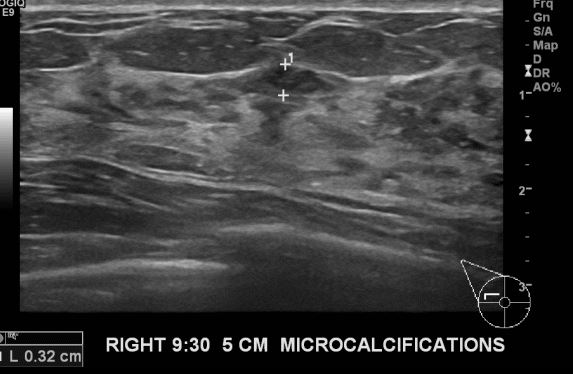

상기환자 9:30분 거리의 미세석회 포함부위 맘모톰 시행하여 유관암 진단 되었습니다.